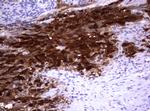

TYMS Antibody in Immunohistochemistry (Paraffin) (IHC (P))

TYMS Antibody (CF801760) in IHC (P)

Immunohistochemical staining of paraffin-embedded human lymphoma tissue using anti-TYMS mouse monoclonal antibody. (Heat-induced epitope retrieval by 10mM citric buffer, pH6.0, 120°C for 3min, TA801760) {{ $ctrl.currentElement.advancedVerification.fullName }} 验证信息 View more